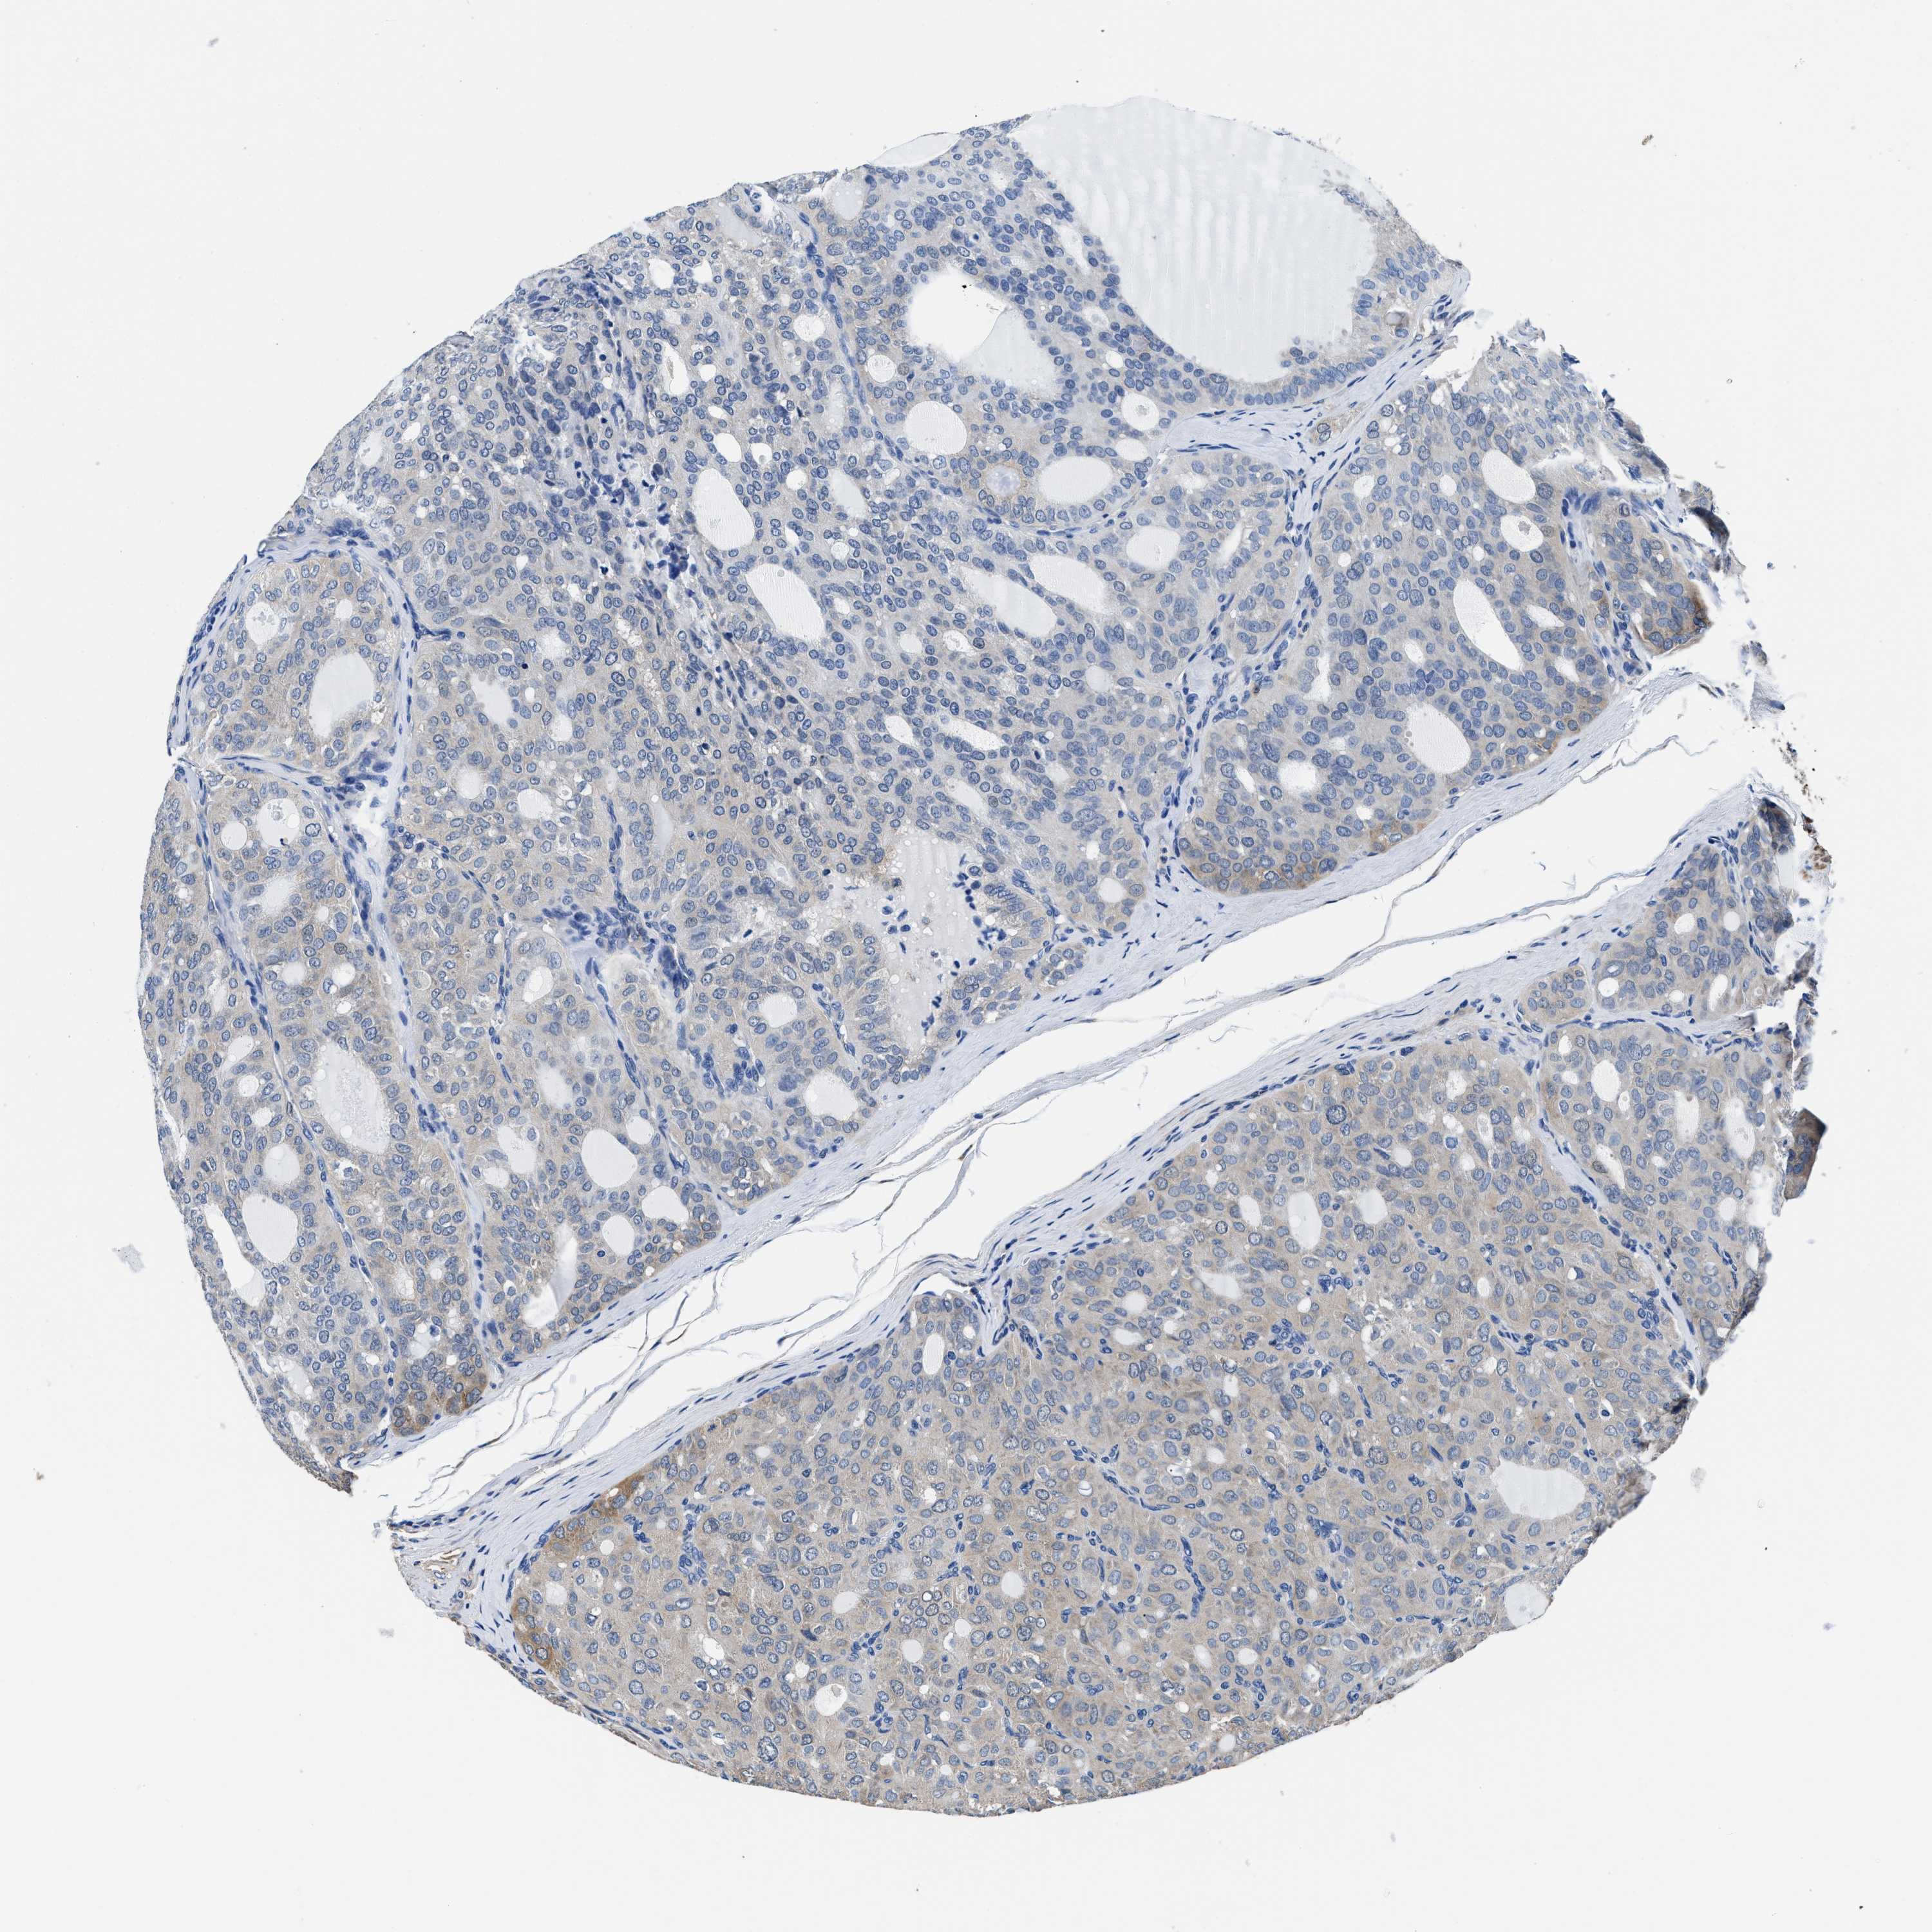

THYROID CANCER - Protein expressioni

A mouse-over function shows sample information and annotation data. Click on an image to view it in a full screen mode. Samples can be filtered based on level of antibody staining by selecting one or several of the following categories: high, medium, low and not detected. The assay and annotation is described here.

Note that samples used for immunohistochemistry by the Human Protein Atlas do not correspond to samples in the TCGA dataset.

Antibody stainingi

Antibody staining in the annotated cell types in the current human tissue is reported as not detected, low, medium, or high, based on conventional immunohistochemistry profiling in selected tissues. This score is based on the combination of the staining intensity and fraction of stained cells.

Each image is clickable and will lead to virtual microscopy that enables deeper exploration of all samples and also displays staining intensity scores, fraction scores and subcellular localization as well as patient and tissue information for each sample.

Antibody HPA015634

Antibody HPA021506

Staining

High

Medium

Low

Not detected

Intensity

Strong

Moderate

Weak

Negative

Quantity

>75%

75%-25%

<25%

None

Location

Nuclear

Cytoplasmic/membranous

Cytoplasmic/membranous,nuclear

Papillary adenocarcinoma, NOS

Follicular adenoma carcinoma, NOS